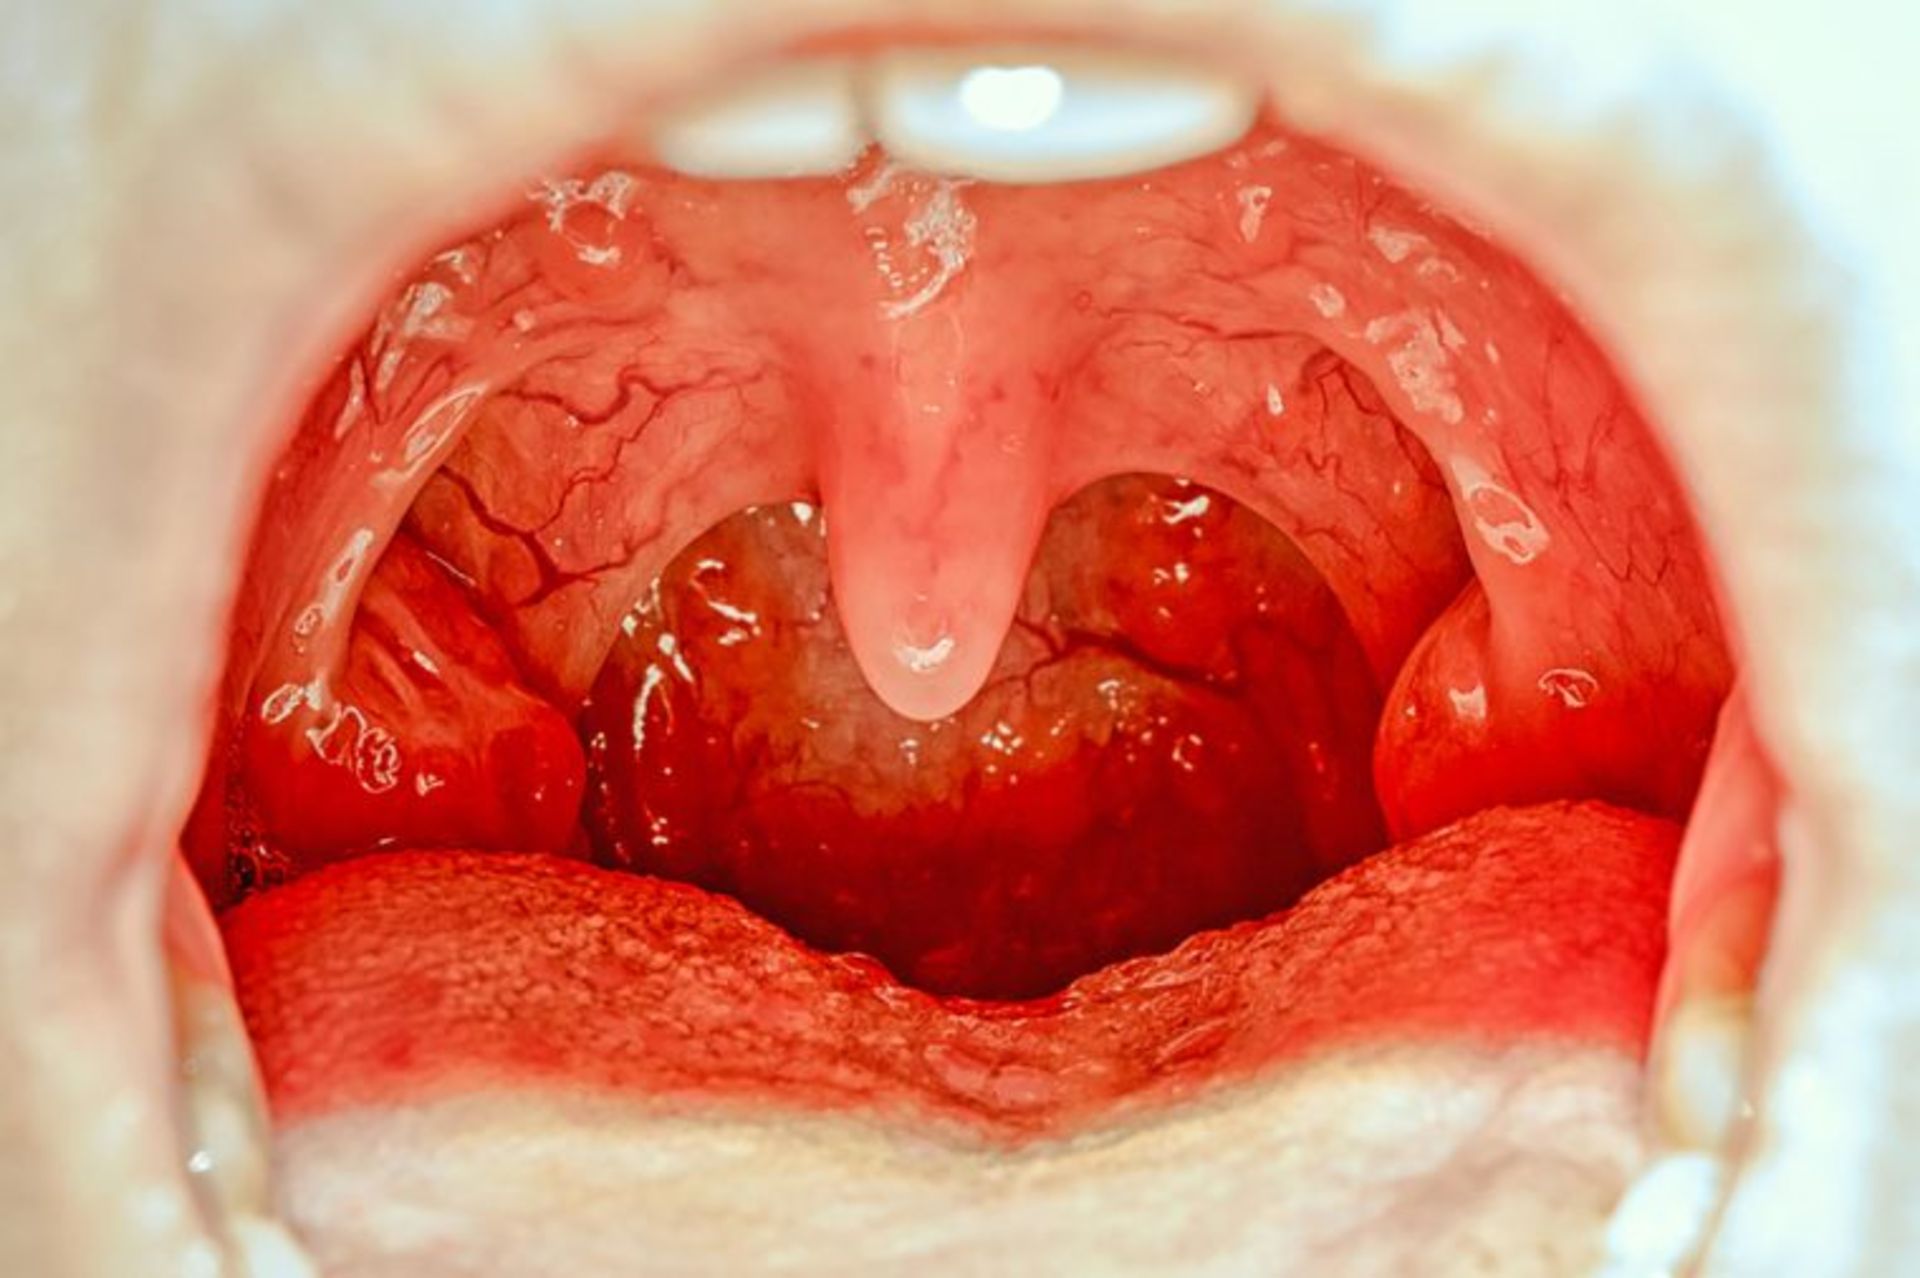

لوزه‌ها

زبان کوچک / Uvula

این غده‌ها، ما را در برابر ویروس‌ها و باکتری‌هایی که روزانه وارد بدنمان می‌شوند، محافظت می‌کنند. در مواردی که لوزه‌ها برای مدت طولانی متورم باقی بمانند، خود می‌توانند باعث عفونت شوند. در این‌ گونه موارد، پزشکان توصیه می‌کنند که آن‌ها را از حلق خارج کنیم. با این وجود نقش ایمنی لوزه‌ها در بدن هنوز به‌طور کامل مشخص نشده است. این غده‌‌ها که بخشی از سیستم لنفاوی هستند از عفونت‌هایی که از طریق بینی و دهان وارد می‌شوند، محافظت می‌کند اما در صورت تجمع زیاد باکتری‌ها، خود نیز به عنوان سد دفاعی عمل خواهند کرد.

چون لوزه‌ها بخش کوچکی از سیستم دفاعی بدن را تشکیل می‌دهند، کسانی که بیماری‌های مزمن یا مشکلات تنفسی دارند، می‌توانند با عمل جراحی آنها را بردارند. امروزه حدود ۵۰۰ هزار عمل برداشت لوزه در ایالات متحده‌ی آمریکا انجام می‌شود، که در مقایسه با ۱ میلیون عمل جراحی دهه‌ی ۱۹۷۰، کاهش پیدا کرده است و پزشکان در مقایسه با قبل، نسبت به پیشنهاد برداشت لوزه‌ها برای کنترل عفونت، با احتیاط عمل می‌کنند.